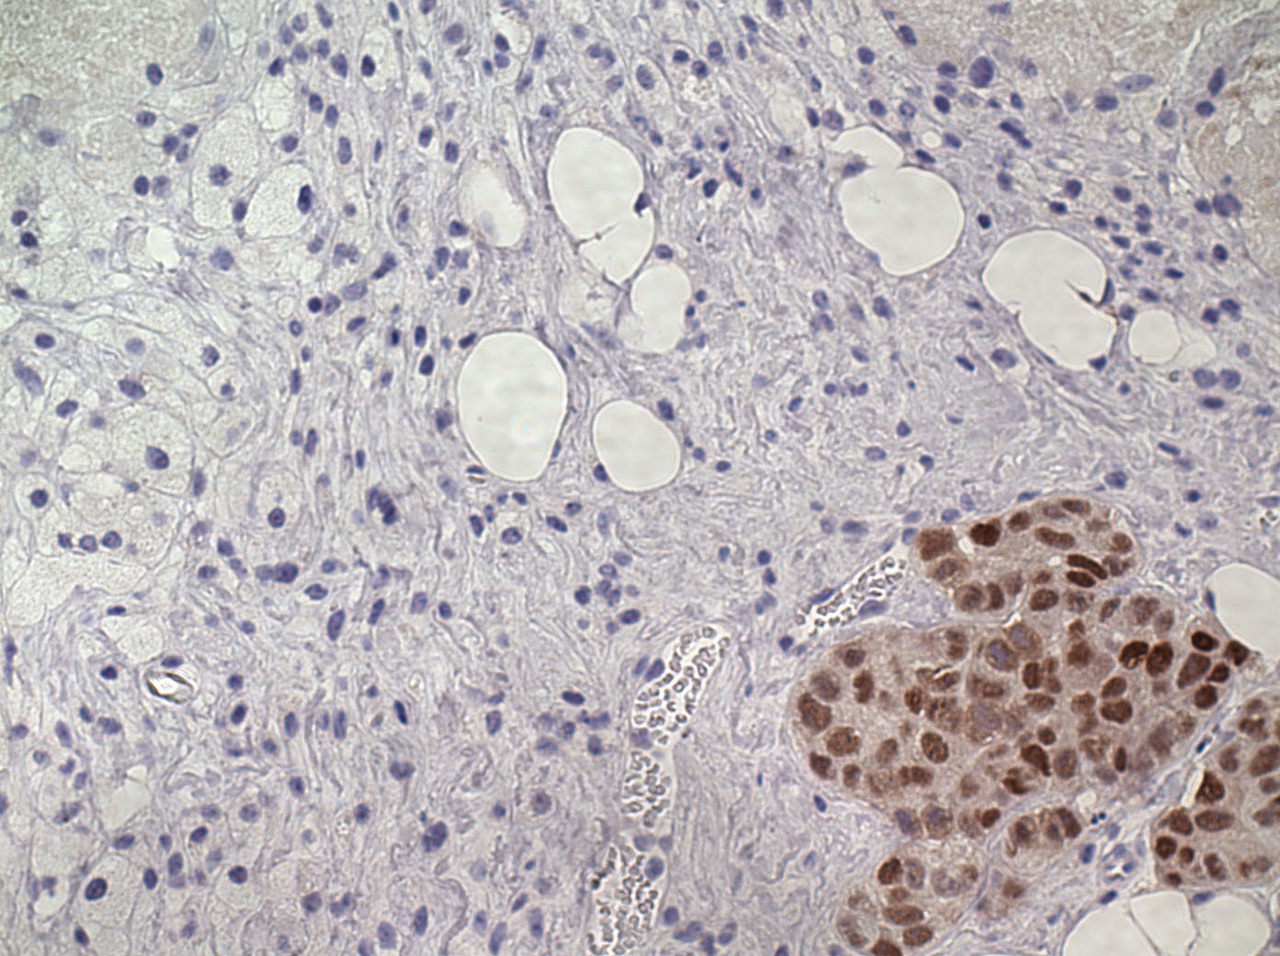

We started by characterizing cell line and tumor models that respond to treatment with estrogen.  We found that all of the models overexpress ER, and most  also have genomic amplification of the gene encoding ER. These high levels of ER expression are required for resistance to estrogen deprivation, but are also required for therapeutic response to estrogen. We also found that in order to elicit a therapeutic effect, estrogen must stimulate very high levels of ER activity in ER-overexpressing cells. This suggests that there is an optimal window of ER activity, and either too much or too little ER activity inhibits the growth of breast cancer cells.